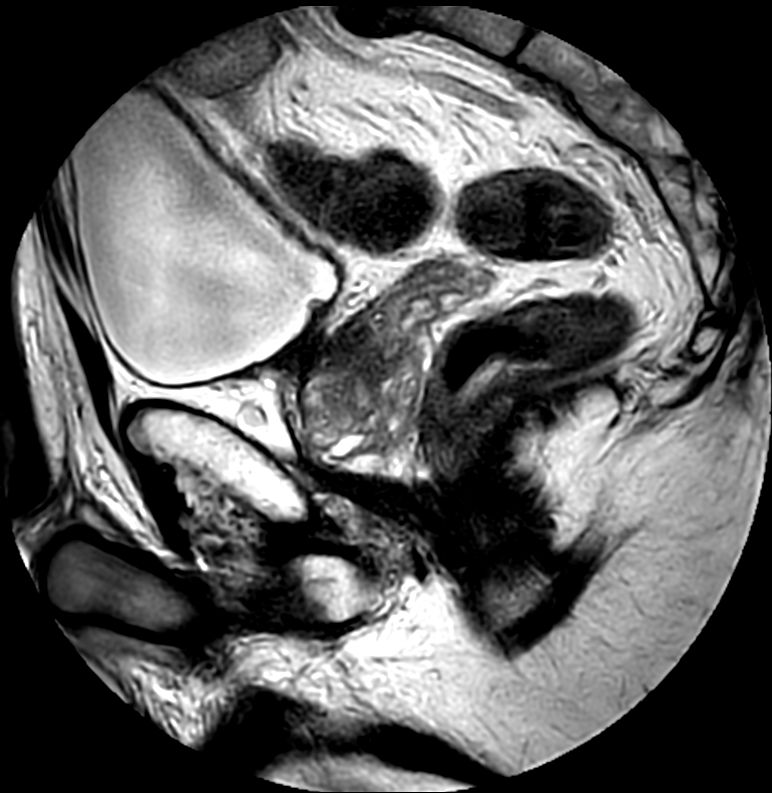

For prostate exams, the MSK M coil can be used in combination with the posterior coil, delivering exceptional quality MR images and high patient satisfaction.

Premium signal-to-noise ratio is achieved via dStream, providing outstanding image resolution.